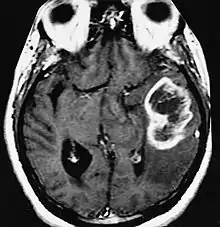

| An example of a ring-enhancement around a lesion in gliobastoma. In tumefactive multiple sclerosis, the ring-enhancement is open, not forming a complete ring. |

These atypical lesion characteristics include a large intracranial lesion of size greater than 2.0 cm with a mass effect, edema and an open ring enhancement. A mass effect is the effect of a mass on its surroundings, for example, exerting pressure on the surrounding brain matter. Edema is the build-up of fluid within the brain tissue. Usually, the ring enhancement is directed toward the cortical surface.[2] The tumefactive lesion may mimic a malignant glioma or cerebral abscess causing complications during the diagnosis of tumefactive MS. T2-hypointense rim and incomplete ring enhancement of the lesions on post-gadolinium T1- weighted imaging on brain MRI enable accurate diagnosis of TDL[3]

Diagnosis of tumefactive MS is commonly carried out using magnetic resonance imaging (MRI) and proton MR spectroscopy (H-MRS). Diagnosis is difficult as tumefactive MS may mimic the clinical and MRI characteristics of a glioma or a cerebral abscess. However, as compared to tumors and abscesses, tumefactive lesions have an open-ring enhancement as opposed to a complete ring enhancement.[1] Even with this information, multiple imaging technologies have to be used together with biochemical tests for accurate diagnosis of tumefactive MS.[36]